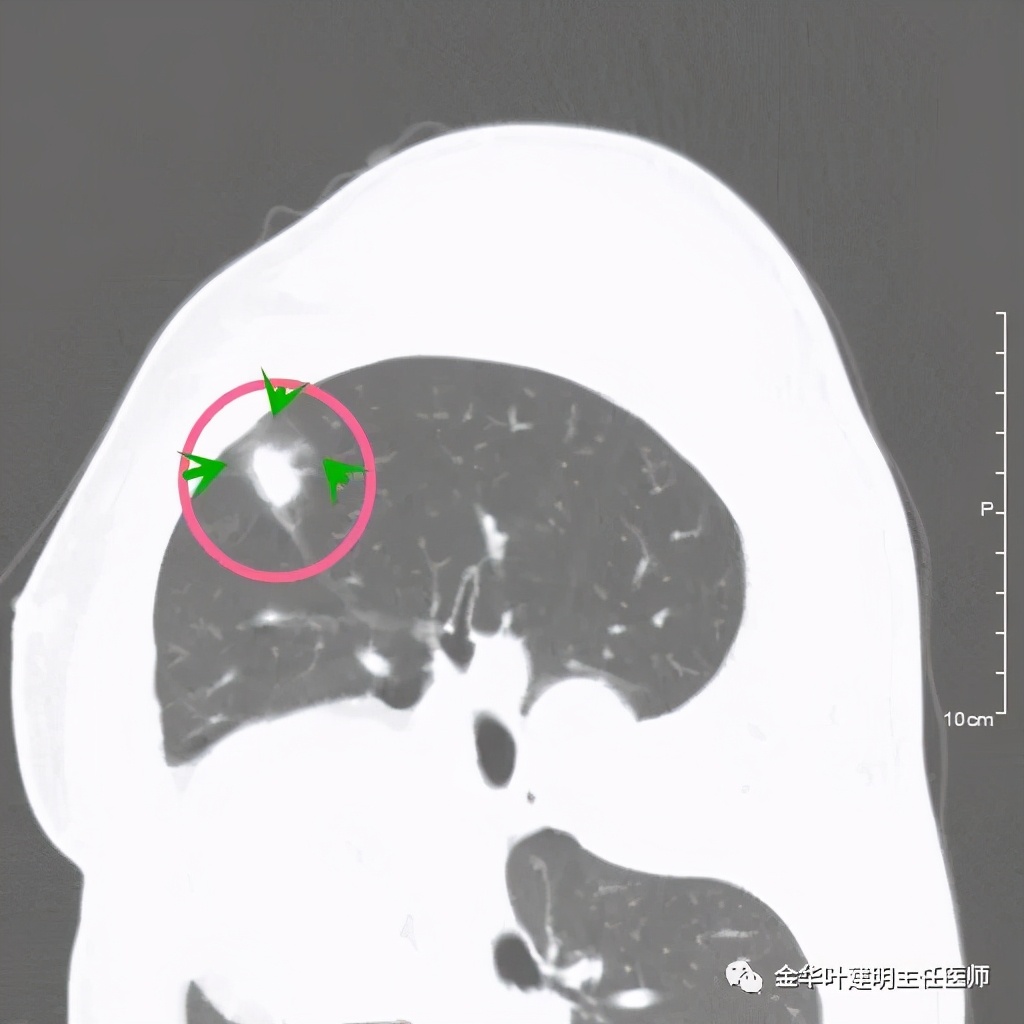

病灶实性,但收缩力弱,绿色箭头示病灶边缘有一圈晕征(模糊且均匀)

病灶实性,但收缩力弱,没有细毛刺征,实性部分比较圆润,绿色箭头示病灶边缘有一圈晕征(模糊且均匀)

此层面相对最不舒服,病灶表面不平整。桔色箭头示血管进入病灶,但仍有绿色箭头示病灶有晕征(边缘是模糊的,不似肿瘤那种细毛刺且相对清楚轮廓)

紫色箭头示病灶的边缘向内凹陷,说明无膨胀性,绿色示晕征,粉色箭头指向病灶

此层面示病灶呈三角形,缺乏膨胀性,边缘较直,没有毛刺征,实性部分没有收缩纠集感,绿色箭头示晕征